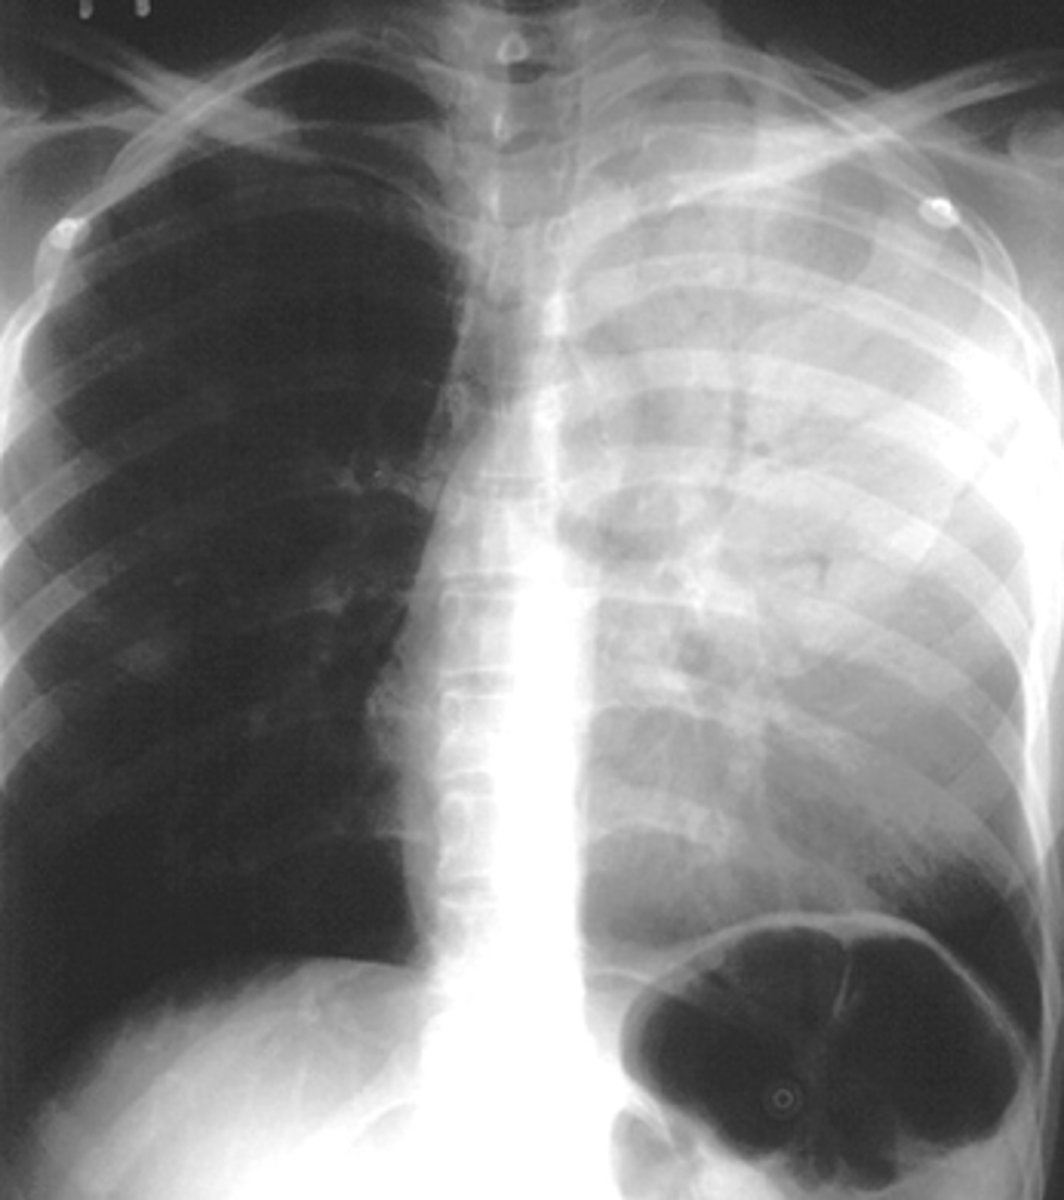

Bilateral pleural effusion

air bronchogram- alveolar consolidation LUL